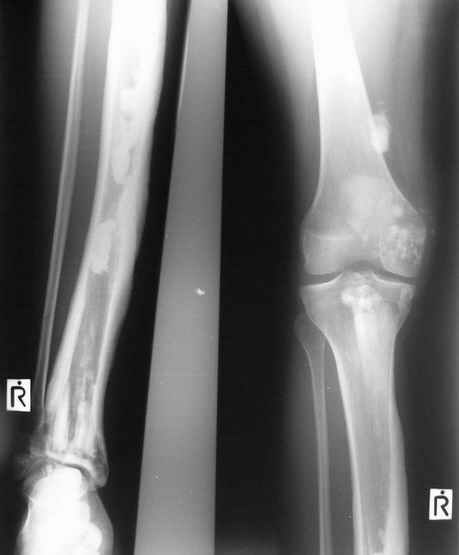

Отдельные случаи мелореостоза отличаются друг от друга по степени и форме склеротических участков; каждый случай

представляет свои неповторяемые особенности. В более тяжелых случаях поражения нижней конечности захвачена и

соответствующая половина таза, при локализации в верхней конечности - часть лопатки. Из парных костей поражается,

как правило, только одна: это большеберцовая или малоберцовая кость, лучевая или локтевая кость, но никогда не

обе кости одновременно. Мы наблюдали изолированные поражения не только периферических, но и ближе к туловищу

расположенных костей, например, бедра без вовлечения в процесс голени, или половины таза с соответствующей

половиной нижних поясничных позвонков и проксимальной части бедренной кости. Другими словами, в редких случаях

объем изменений совсем не возрастает по направлению к.периферии. В самых редких случаях в какой-то ничтожной

степени в процесс может быть вовлечен череп (часть нижней челюсти). Поражения ребер мы ни разу не наблюдали.

Измененный корковый слой, а также уплотненные эпифизы и мелкие губчатые кости приобретают плотность слоновой

кости. Корковый слой утолщается как в сторону костномозгового канала (эндостальная форма), в большей или меньшей

степени суживая его, так и наружу (периосталь-ная форма), возвышаясь над нормальным уровнем кости и увеличивая

этим ее наружный диаметр. Поверхность "наплывов" слегка волниста, с гребневидными возвышениями и углублениями, но

всегда резко конту-рируется. Склеротические полосы и ленты бывают чаще всего сплошными, но нередко они

прерывисты, расслоены. Иногда наблюдается некоторое удлинение костей и их небольшая дугообразная деформация, а

подчас и наоборот - очень незначительное укорочение. Это зависит, надо думать, от участия энхондрального хряща,

раздражения или торможения его функции. Костная ткань в соседстве со склеротическими полосами и островками

сохраняет нормальный рисунок или часто слегка поротична, так что граница между затемненными склеротическими

лентами и костным фоном очень резка. Иногда в мягких тканях таза или области плечевого пояса развиваются

неправильные шаровидные плотные костные массы, а при прогрессировании болезни подобные островки появляются и в

окружности суставов, которые сами по себе особых изменений не представляют. Патологические переломы при

мелореостозе не описаны. Мы также по собственному опыту и по литературным данным не знаем озлокачествления при

мелореостозе. Течение болезни вообще вполне доброкачественное и общее предсказание благоприятное.